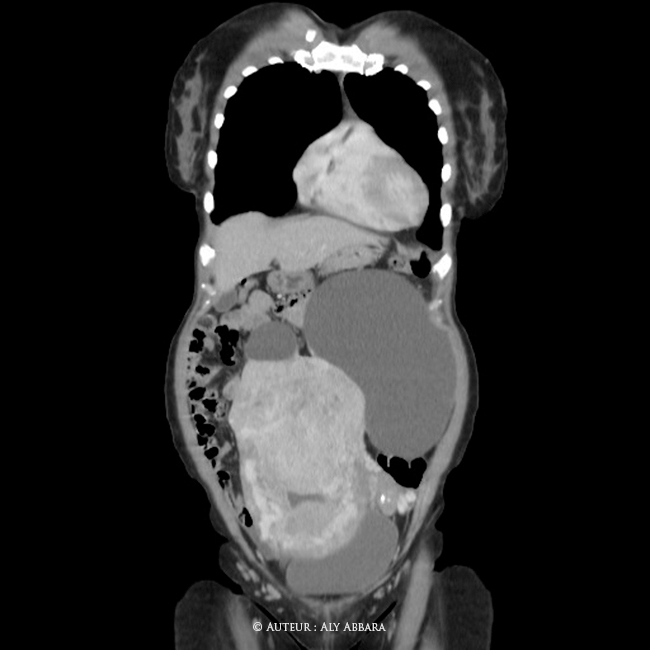

Utérus polymyomateux de 3800 g comportant deux volumineux myomes enkystés - Imagerie par scanner - coupes multiplans

Images Scanner (coupe : coronale ; sagittale et axiale) montrant un volumineux utérus polymyomateux pesant environ 3800 grammes et comportant deux myomes enkystés (kystes sous séreux utérins par dégénérescence kystique de fibromes) de 95 cm3 et 1661 cm3 de volume

L'exploration chirurgicale montre qu'il s'agit d'un volumineux utérus pesant (avec les contenus des kyste) environ 3800 grammes ; avec la présence de deux formations kystiques sous-séreux de la paroi utérine évoluant au niveaux du pôle supérieur de l'utérus (à gauche d'environ 18 - 19 cm de grand axe et à droite de d'environ 7 cm de grand axe)